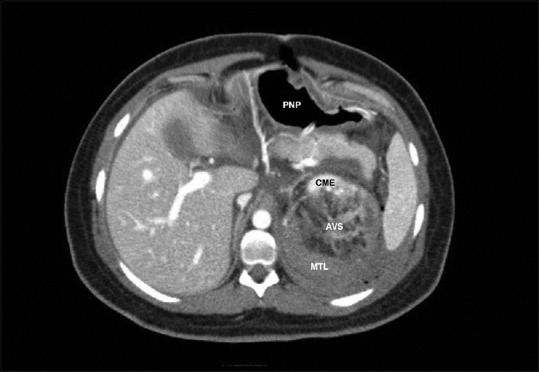

Wunderlich syndrome is characterized by the presence of abdominal pain, hematuria, and hypovolemic shock. We report a rare case of a 25-year-old pregnant woman, who came to the emergency department due to the sudden onset of low back pain and diaphoresis. The patient, during medical evaluation, experienced an altered state of consciousness. Diagnosed with hypovolemic shock, she was admitted to the operating room, where examination of the abdominal cavity revealed a left retroperitoneal hematoma. Damage control surgery was performed, but given the postoperative clinical deterioration, computerized tomography angiography of the abdomen was performed, showing a mass-like lesion arising from the upper pole of the left kidney, consistent with Wunderlich syndrome. Left nephrectomy was the definitive treatment for the 10-cm renal angiomyolipoma. Since Wunderlich syndrome is a potentially lethal entity, CT is usually the preferred diagnostic approach, and supra-selective vascular embolization is the first-line treatment.